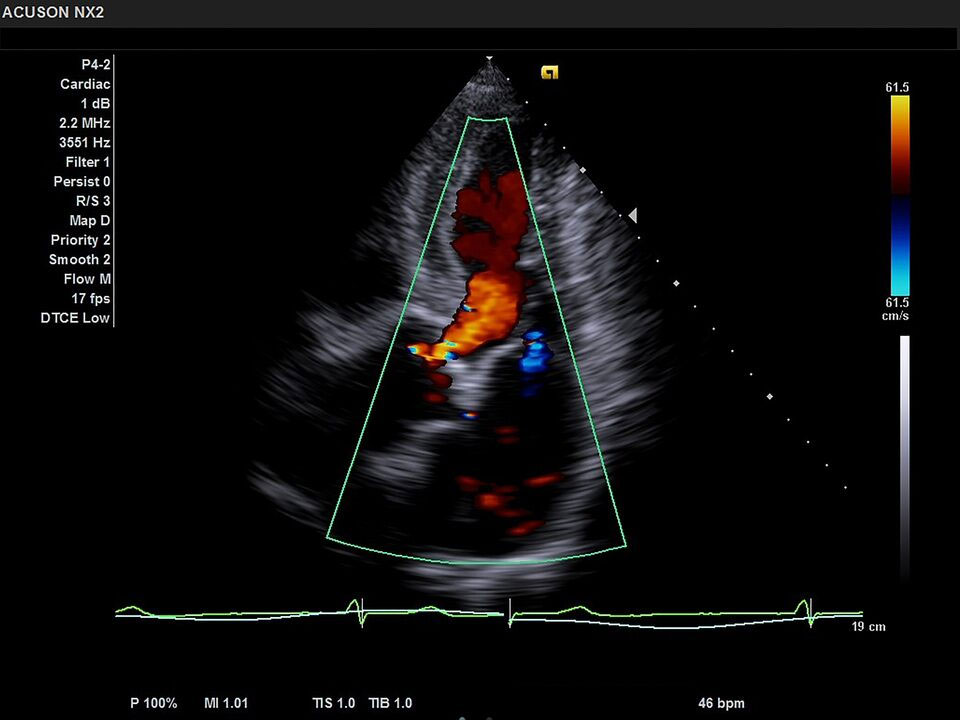

- Секторный - P4-2;

Митральная регургитация Быстрая оценка митрального клапана в 2D-режиме и режиме ЦДК с использованием режима разделения экрана. |

Аортальная регургитация Оценка функции клапана аорты с отличной детализацией и высокой чувствительностью режима ЦДК. |